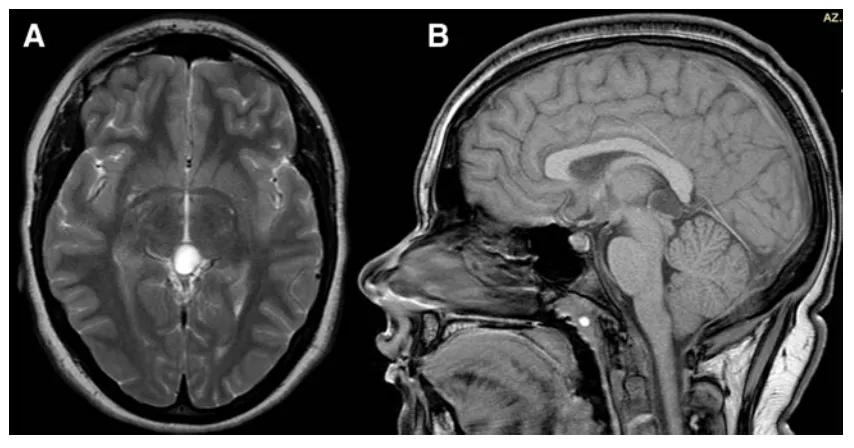

未曾预料,宝贝女儿偶尔提到的头痛、怕光、视物模糊,根源竟在于颅内病变。MRI检查显示豆豆的松果体区存在一直径13毫米的囊肿。

复查MRI时,医生微微皱眉:"囊肿已增长至16毫米,虽仅增大3毫米,但结合症状加重,建议手术干预。"

术后过程平稳,豆豆仅出现短暂视力模糊,24小时内自行恢复。病理检查提示为松果体囊肿,周围可见毛细胞样胶质层包绕。术后6个月随访显示豆豆头痛无复发,恢复良好。